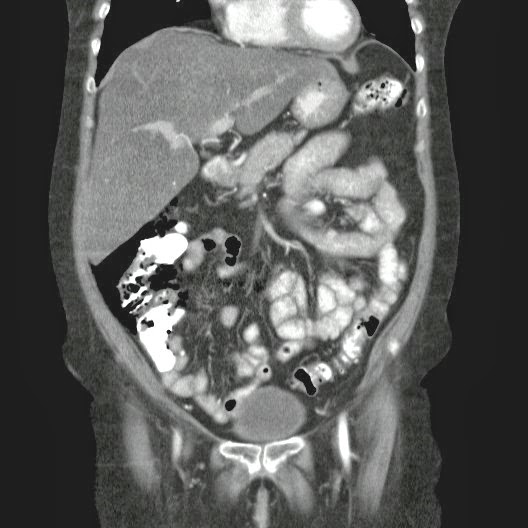

- ¿Hallazgos Escanografia?

2. Hay una colección de la pared abdominal en el flanco derecho, que realza en la periferia con el contraste, e intraabdominal tiene aire pero no me parece colección intraabdominal porque la grasa no está alterada.

3. Recomendado: Drs. JOSÉ M. ZUÑIGA A.1, FRANCO ORELLANA G.1, MARCELO CASTRO S.3, ROLANDO SEPÚLVEDA D.4, HORACIO RÍOS R.4, Int. VELIA SALDÍAS H.2. Neumatosis Intestinal: Caso Clínico-Radiológico. Pneumatosis intestinalis. A case report. Rev Chil Cir v.61 n.1 Santiago feb. 2009